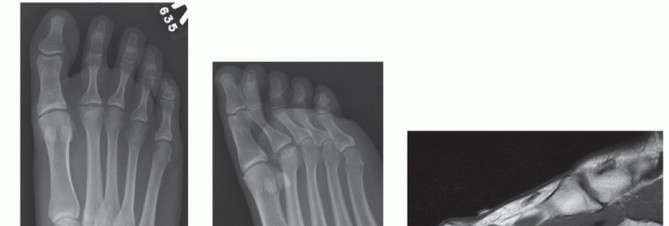

DEFINITION Hallux valgus is a static subluxation of the first metatarsophalangeal (MTP) joint with medial dev…

SURGICAL MANAGEMENT Roger A. Mann Jeffrey A. Mann The distal soft tissue procedure and proximal metatarsal os…

DEFINITION Symptomatic hallux valgus associated with a first intermetatarsal angle greater than 15 degrees is…

SURGICAL MANAGEMENT Roland Walker Paul Hamilton Sam Singh The primary indication for a scarf osteotomy is sym…

BACKGROUND The proximal opening wedge osteotomy is one of the more than 150 procedures described for the trea…